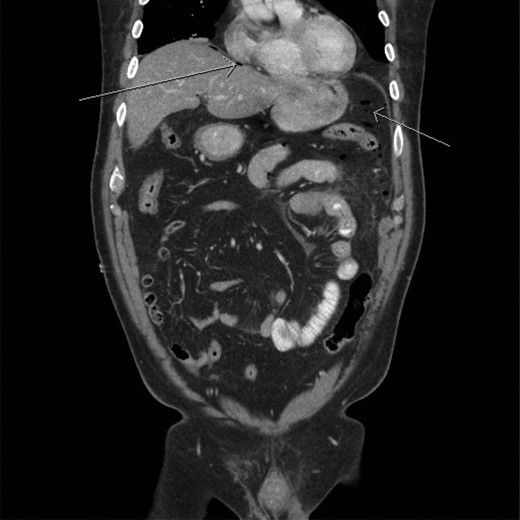

A CT scan demonstrated significant soft tissue stranding/edema of the omentum in the left hemi-abdomen. In addition, there was mild ascites and multiple scattered locules of air (Figs 3–5). No other abnormality of the small or large bowel was identified. He was admitted for observation and broad-spectrum antibiotic therapy was initiated. On post admission day 2, he became diffusely peritonitic, febrile with a temperature of 39.1°C and his oxygen requirements increased to 12 l/min.

CT scan (frontal view) demonstrating multiple locules of air (arrows).

Our case demonstrates the diagnostic dilemma that accompanies delayed bowel injuries. Laboratory tests often give nonspecific results that seldom point to a diagnosis [1]. Imaging studies also fail to establish the etiology. Our CT scan failed to demonstrate significant intraperitoneal free air (Figs 3–5). In addition, oral contrast was utilized, but gross extravasation was not identified.